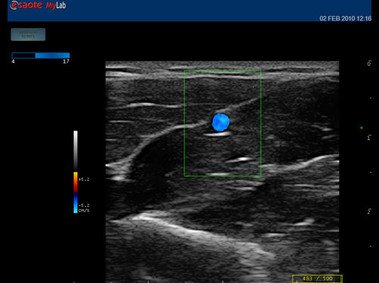

12”-Full-Touchscreen Farbdoppler

Das MyLab™One steht für das revolutionäre „Arm-held“ Hochleistungs-Ultraschallsystem mit 12”-Full-Touchscreen. Aufgrund seines geringen Gewichts und der Tragbarkeit kann es auch ohne Arbeitsfläche verwendet werden. Eine einzelne Person kann dieses Gerät aufgrund seiner einzigartigen Funktionen allein und selbstständig bedienen.

Das Ultraschallsystem MyLab™One zeigt exemplarisch den modernen Bedarf an Diagnosekapazitäten in verschiedenen Anwendungsbereichen: Radiologie, Kardiologie, Phlebologie, Frauenheilkunde, Orthopädie, Regionalanästhesie, Sportmedizin, Interventionell, Rheumatologie, Erste Hilfe, Notfallmedizin, Vaskuläre Reihenuntersuchungen, Allgemeinpraxis.

Der intuitive Touchscreen bietet dem Benutzer schnellen und einfachen Zugang zu allen Steuerungsfunktionen. Mit der beeindruckenden Bildqualität und einem kompakten Design wird MyLab™One zur idealen Ultraschalllösung am Point-of-Care.